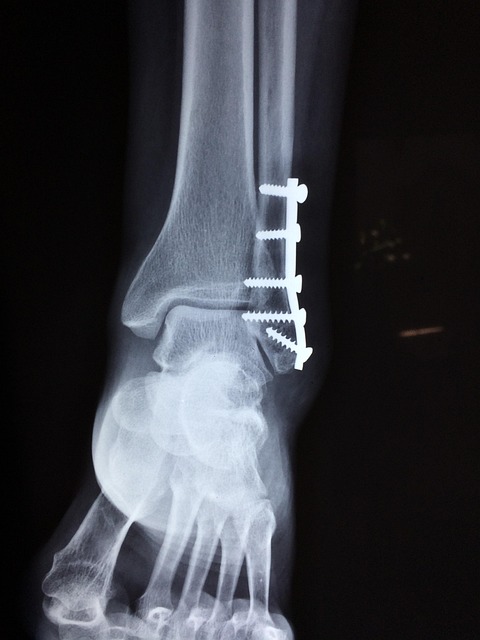

손가락 마디 통증이 계속된다면, 혼자서 고민하기보다는 병원에 가서 정확한 진단을 받아보는 것이 가장 중요해요. 의사 선생님은 X-ray, 초음파, MRI 같은 영상 검사를 통해 손가락 관절의 상태를 자세히 살펴볼 수 있답니다.

특히 가운데 손가락 통증처럼 특정 부위가 유독 아프다면 더욱 세밀한 검사가 필요할 수 있어요. 조기에 진단받고 적절한 치료를 시작하면 통증을 줄이고 더 큰 문제로 발전하는 것을 막을 수 있어요.